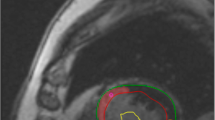

T1 quantification

T1 maps were constructed offline using MRmap [14, 15] a customized software program written in Interactive Data Language (IDL; RSI International, Boulder, CO, USA). The position of the source images was initially manually adjusted to correct for potential misregistration. A curve fit of the MOLLI source images was then performed, with automatic calculation of T1 values for each pixel. A T1 parametric map was subsequently generated and used for further analysis. The parametric maps were evaluated in CMR42. Freehand ROI’s of approximately 10–20 pixels were placed in scar tissue, remote myocardium and blood for measuring the averaged T1 time in this tissue. Reference for scar delineation was the LGE image in the same plane (Fig. 1).